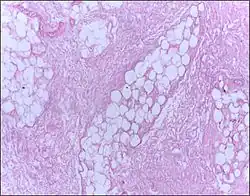

![]() |

Lipoma | Micrograph of a lipoma showing fat cells. | Category: Histopathology of lipomas | Lipoma |